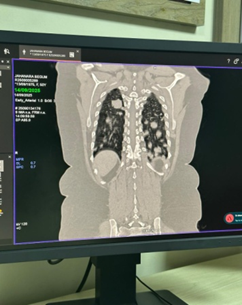

Case Presentation: A 50-year-old female presented with anorexia and cervical lymphadenopathy came for evaluation and management. Chest radiograph and CT scan demonstrated multiple bilateral pulmonary nodules without abdominal organ involvement. Core biopsy of a pulmonary lesion confirmed the diagnosis of NHL, B-cell type.

• Chest radiograph revealed multiple nodular opacities in both lung fields.

• CT chest demonstrated numerous, variable-sized nodules scattered throughout both lungs, with no mediastinal mass, pleural effusion, or consolidation.

• CT abdomen showed normal hepatosplenic and abdominal organ morphology.